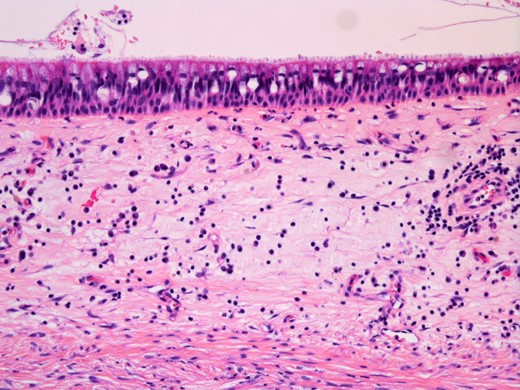

Histopathological findings of the cyst. Haematoxylin and eosin staining showing pseudostratified ciliated epithelium lining the cyst wall (original magnification ×200).